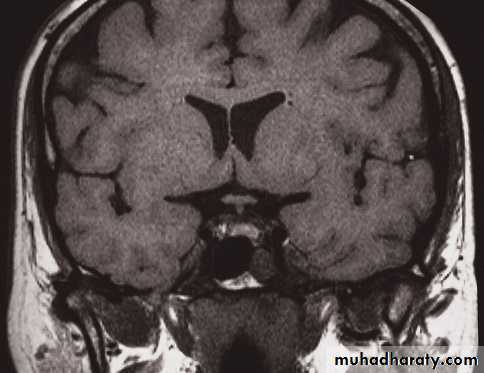

MRI of the brain

• Axial, coronal and sagittal projections are all considered standard• T1-weighted and T2-weighted images.

• It is possible to recognize flowing blood and, therefore, the larger arteries and veins stand out clearly without the need for contrast medium.

• The characteristics of grey and white matter are different, and both are clearly different from the CSF in the ventricular system and subarachnoid space.

• The disadvantages of MRI compared with CT are the inability to show calcification, lack of bone detail, the relative expense of the technique, and the difficulty of monitoring seriously ill patients

• IV contrast in T1 WI

• MRA and MRV, Recent advances of MRI: perfusion, diffusion, spectroscopy, functional MRI, and tractography